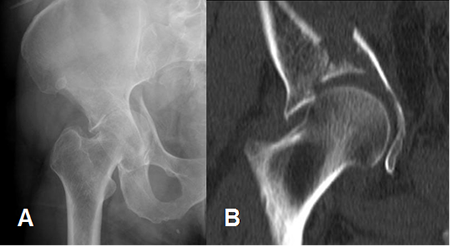

Fig 67. Luxación central de cadera.

A: Rx AP y B: TAC reconstrucción coronal. Fractura conminuta del techo acetabular, con impactación y desplazamiento medial de la cabeza femoral.